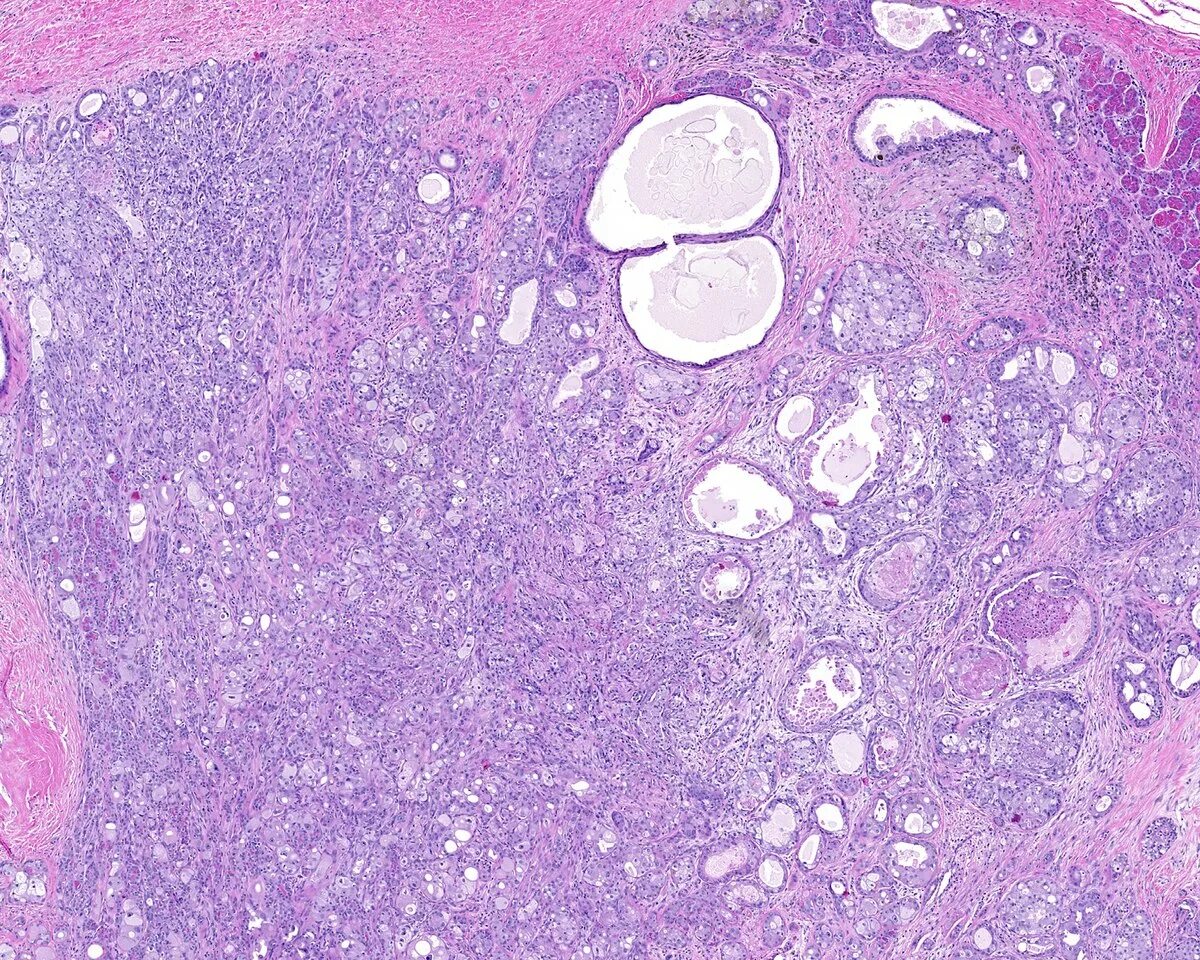

Диффузный аденоз